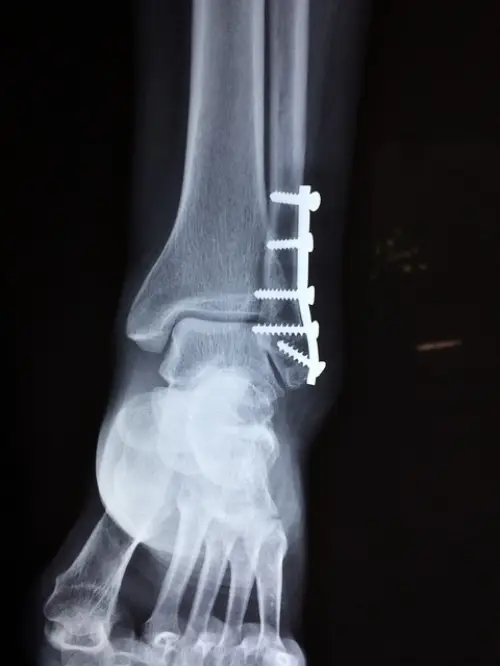

가장 심각한 단계인 3단계 염좌는 인대가 완전히 파열된 상태입니다. 극심한 통증과 함께 심한 부종, 멍이 나타나며 발목에 전혀 체중을 실을 수 없습니다. 발목이 불안정해지고 심할 경우 변형이 관찰되기도 합니다. 이 경우에는 전문적인 의학적 치료가 필수이며, 수술적 치료가 필요할 수 있습니다. 수술 후에는 장기간의 회복과 재활 치료가 진행되어야 하며 회복 기간은 6주에서 3개월 이상 걸릴 수 있습니다.

상기 증상들이 나타났을 때는 X-ray, MRI 등 영상 검사를 통해 인대 파열 정도, 골절 여부, 주변 조직 손상 등을 정확히 확인하는 것이 중요합니다. 이를 통해 적절한 치료계획을 세울 수 있습니다.